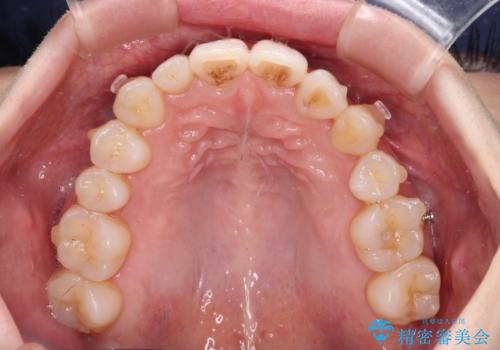

補助装置を併用したインビザラインでの八重歯の抜歯矯正

- 八重歯と奥歯の咬み合わせを気にして来院された患者様です。

インビザラインによる矯正治療を希望されたため、八重歯改善のための抜歯矯正部分は補助装置を併用し、その後はインビザラインにて行うこととしました。

下顎の右側変位が顕著であったため、ワイヤー矯正の方が咬み合わせは改善しやすいのですが、ある程度は時間がかかっても良いとのことであったので、インビザラインにて矯正治療を行うこととしました。

骨格的に下顎が右側に変位していたため、上下正中を合わせることは困難であることは分かっていました。それでも、なるべく合わせるようにとしたため、治療期間は長期間となりました。

長期間とはなりましたが、咬み合わせが改善され、患者様には大変満足していただきました。